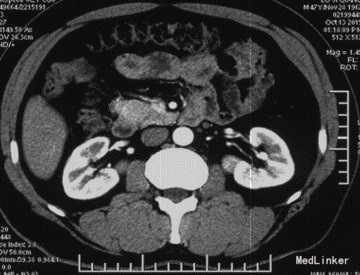

查体:神清,腹软,未及包块,无压痛及反跳痛,神经系统检查未见异常 辅查:外院头颅CT平扫:腔隙性脑梗;胰腺CT平扫:胰头、十二指肠降部稍低密度影,肝内多发小囊肿;上腹部增强CT:胰腺低密度影,考虑良性;肝内多发小囊肿。 入院检查:血、尿、粪常规、肝肾功能、电解质、凝血功能正常;AFP、CEA、CA19-9、CA125、CA15-3、CA72-4均正常;胰岛素78.33mIU/L,C肽 4.91ug/L。腹腔动脉DSA:胰头区富血供肿瘤; 胰腺增强MRI:1、胰头部富血供病变,考虑胰岛素瘤可能性大;2、肝内多发小囊肿。

术前诊断:1、胰头占位性病变(胰岛素瘤?),2、腔隙性脑梗塞,3、肝内多发小囊肿。 术后诊断:1、胰头胰岛素瘤,2、腔隙性脑梗塞,3、肝内多发小囊肿。 入院后控制血糖,完善相关检查在腹腔镜下行胰岛素瘤切除术,术中为、十二指肠、胆囊、横结肠未见异常,胆总管无扩张,打开胃结肠韧带,于胰头健可见大小约2*2cm肿块,表面光滑,边界清,突出于表面,遂行胰岛素瘤切除术超声刀沿肿块边缘完整切除肿块,检查未伤及主胰管。 术后监测血糖,行抗炎、抑酸、补液等对症支持治疗,复查C肽及胰岛素均正常,空腹血糖值正常,康复后出院。